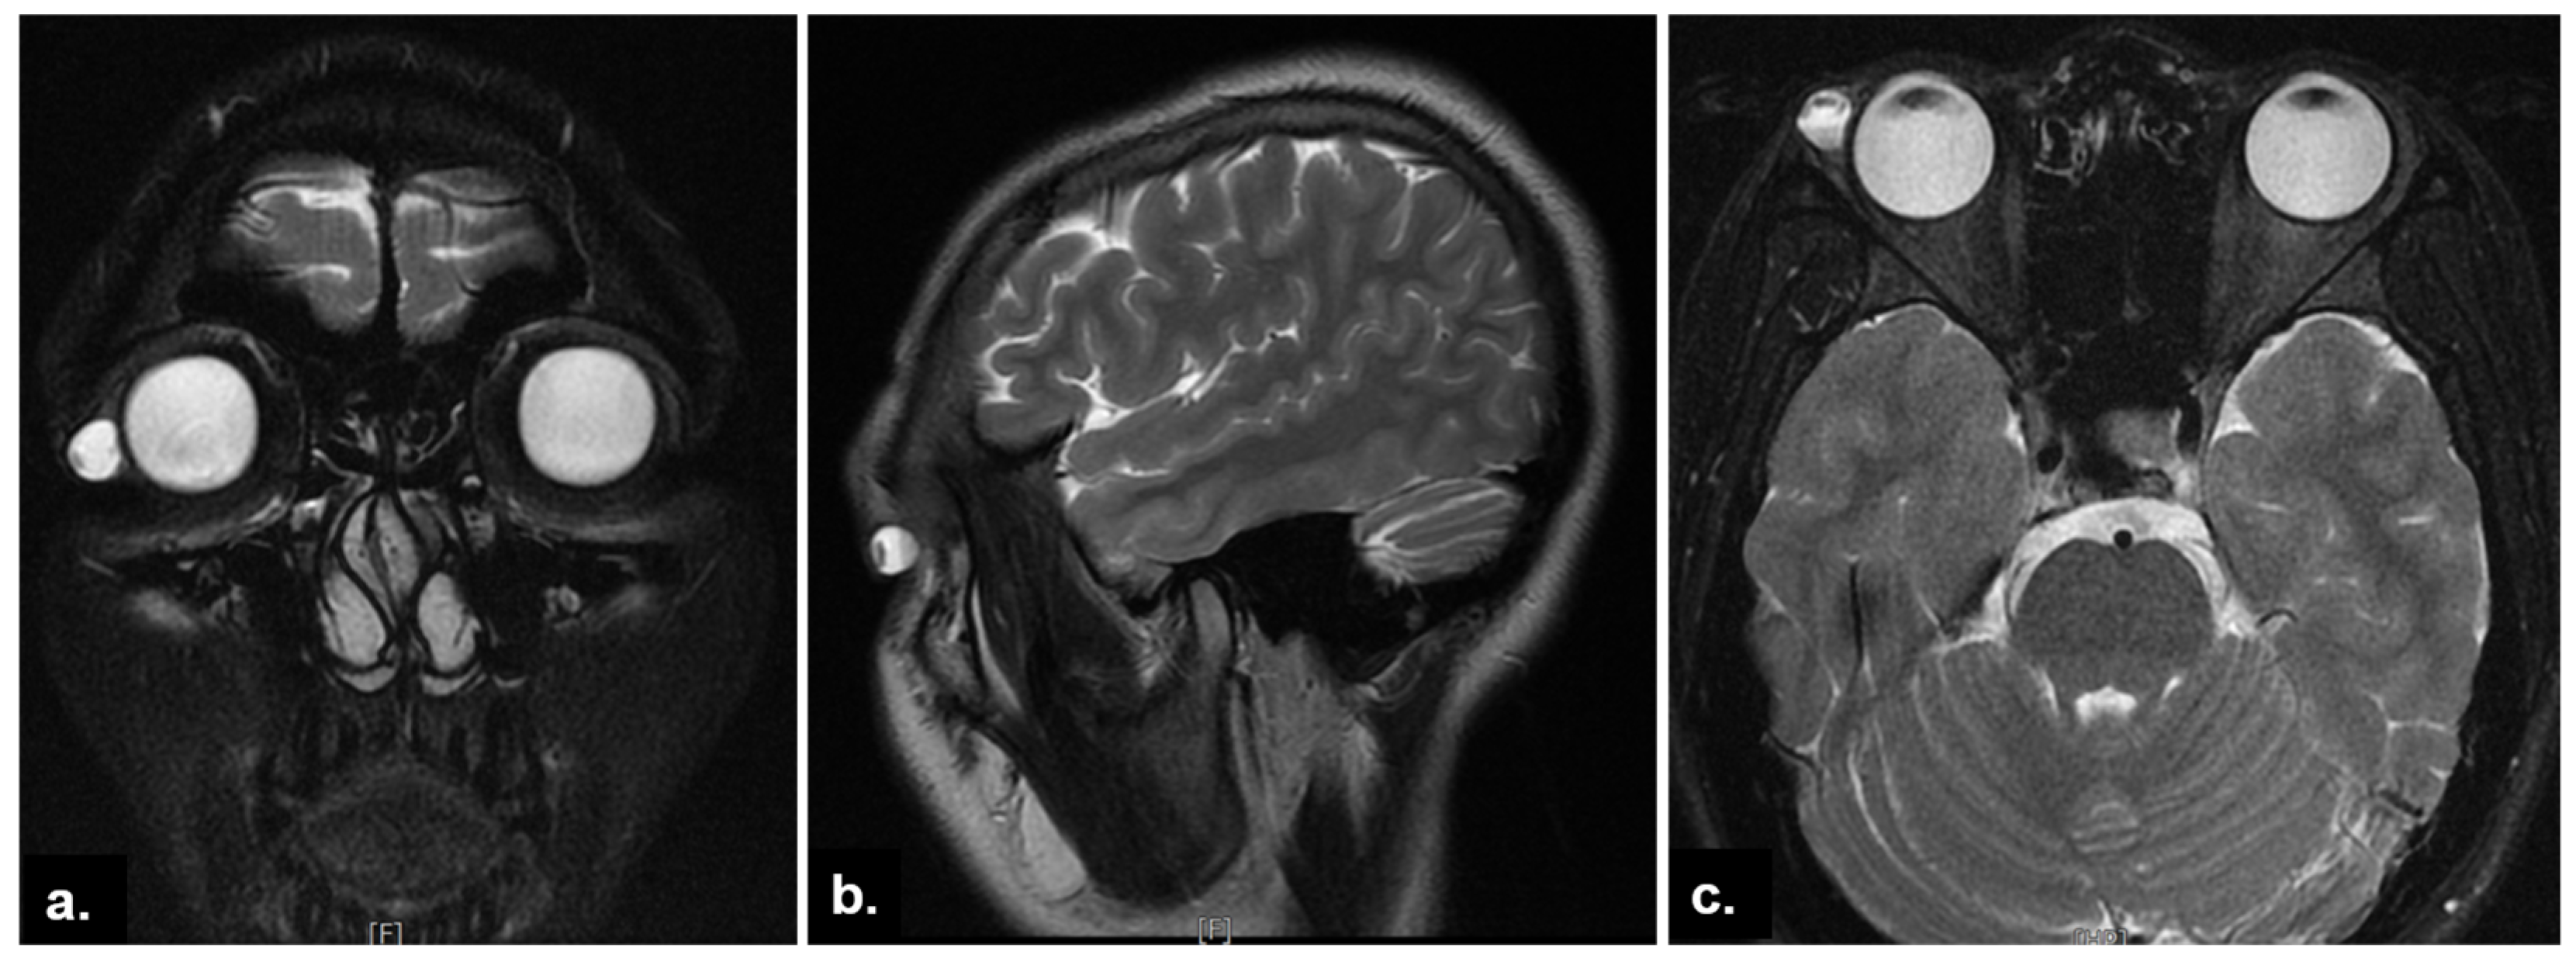

2. Case Presentation